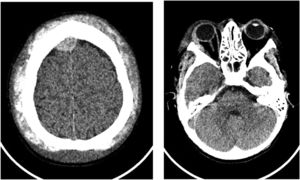

A new CT scan of the skull showed a epidural hematoma in the right frontoparietal high convexity, with 10 mm thickness, pressing the adjacent parenchyma, associated with dense subperiosteal collections near both orbits, two on the right and one on the left, with thicknesses of 11 mm and 10 mm respectively, promoting proptosis of the eyeballs (Figure 1).

Neurosurgical evaluation was requested and magnetic resonance imaging of the skull confirmed the frontoparietal epidural hematomas and extraconal intraorbital hematomas, as well as signs of bone infarction and diffuse heterogeneity of skull's bone marrow. A hypothesis of non-traumatic spontaneous epidural hematoma related to sickle cell anemia was made.